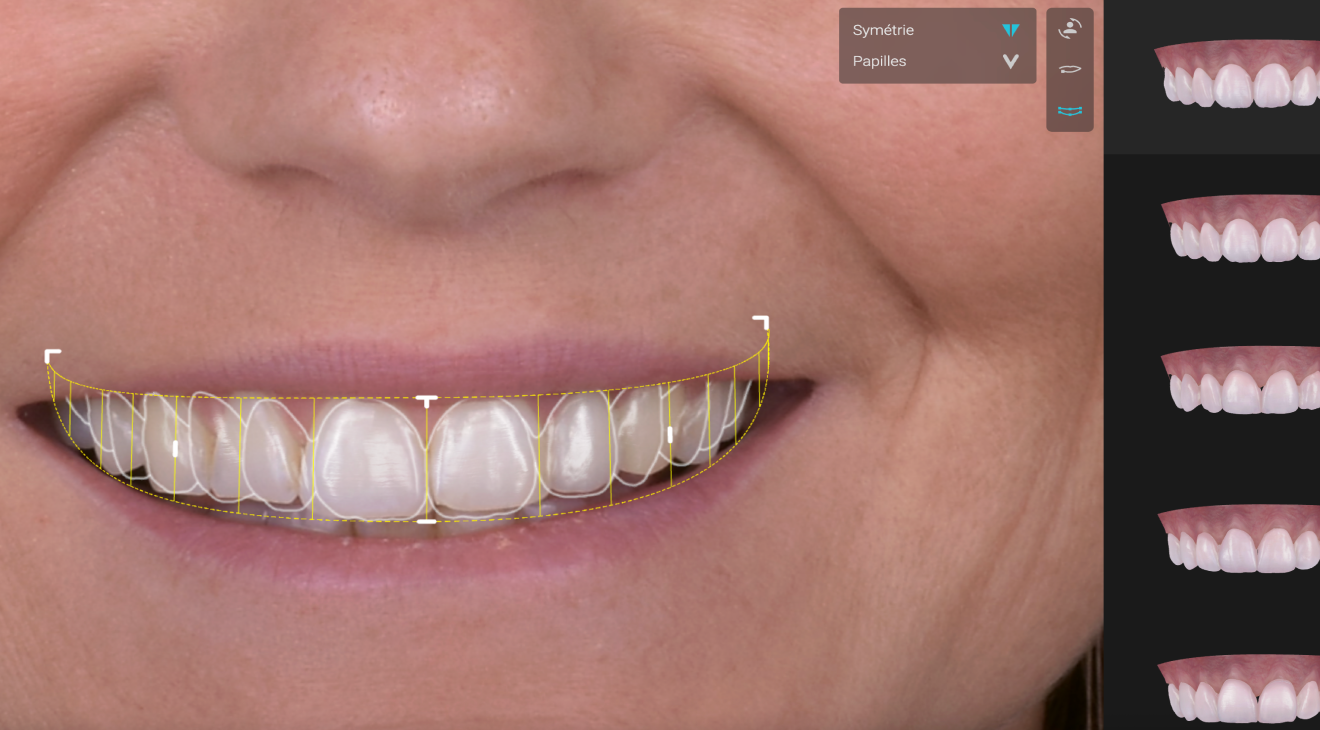

Smilecloud

Smilecloud est une plateforme digitale de planification esthétique qui nous permet de concevoir votre futur sourire de manière précise, personnalisée et prévisible.

Grâce à cette technologie, nous analysons votre visage, vos expressions, vos dents et vos attentes pour créer un projet de sourire harmonieux, naturel et parfaitement adapté à vous.